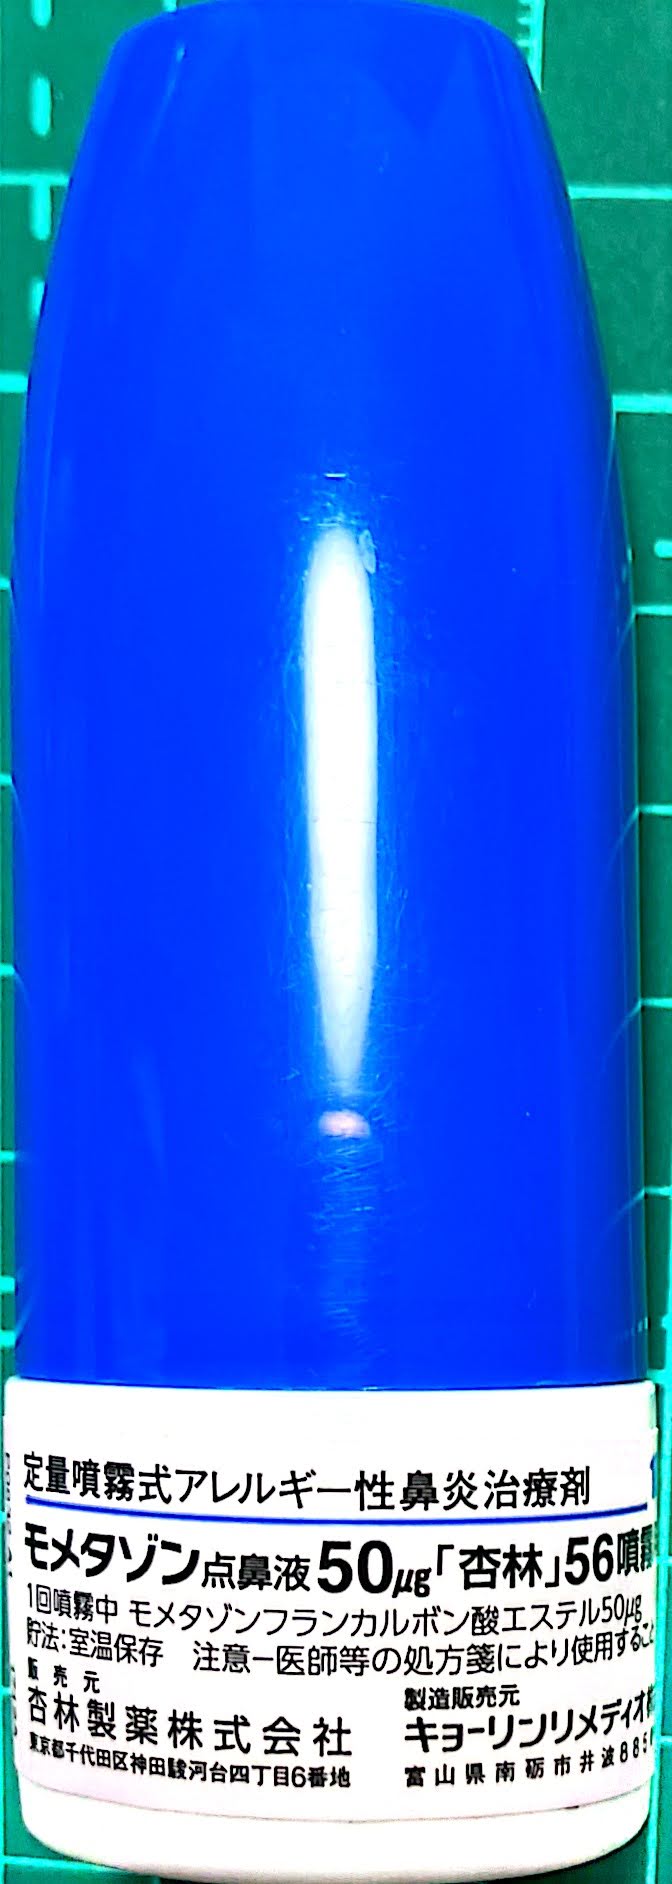

22.10.29 鼻炎薬吸引 モメタゾン点鼻液50μg 噴霧用 5mg10g 杏林 56噴霧用